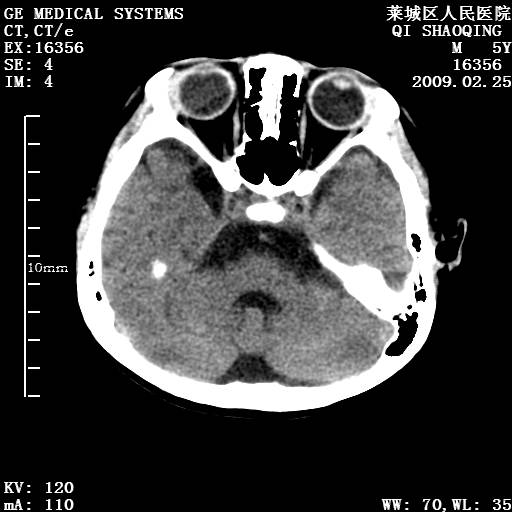

以下是引用wangzhengyuan在2009-2-28 10:22:00的发言:[br]甲状旁腺功能减退引起的脑改变.

以下是引用zsl6918在2009-2-28 10:17:00的发言:[br]首先考虑甲状旁腺功能低下所致,可结合实验室检查明确.另外需除外先天性宫内感染所致.

以下是引用余辉在2009-3-1 9:35:00的发言:[br]患者明显的肢体及智力改变,不支持fahr病,多考虑甲旁低,有可能伴有甲低(呆小症).进一步检查。